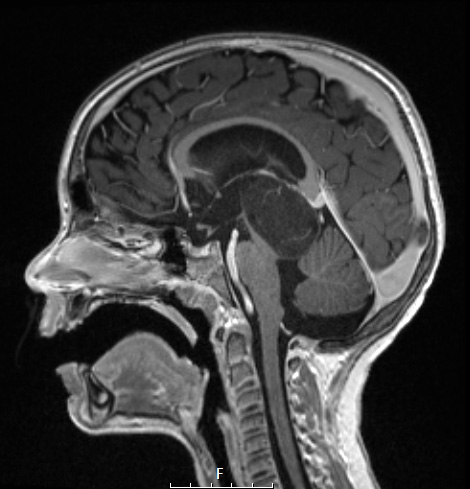

8A4 Angiocentric glioma (Case 8) T1 MPRAGE W A

The tumor is hypointense and fails to enhance with contrast.